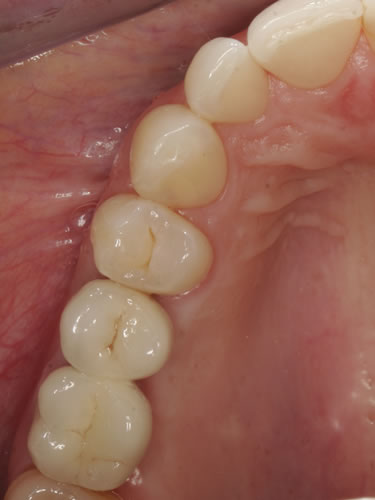

Bei der verkürzten Zahnreihe oder bei größeren Zahnlücken kann eine Versorgung durch so genannte Verbundbrücken erfolgen (Abb. 8.22, 8.23). Dabei werden die künstlichen Pfeiler mit natürlichen Zähnen verbunden. Eine andere Lösung besteht in rein implantatgetragenen Konstruktionen, denen der Zahnarzt den Vorzug geben wird, wenn die noch vorhandenen Zähne gesund sind und deshalb geschont werden sollten (Abb. 8.24. 8.25).

Abb. 8.22: Hybridbrücke auf 4 Implantaten und einem endständigen Zahn.

Abb. 8.23: Zementierte Brücke (Ansicht im Mund).

Für Einzelzahnlücken werden entsprechende Einzelkronen hergestellt. Sie werden, wie bei natürlichen Zähnen auch, mit Zement auf den Implantaten befestigt oder vom Munde her verschraubt (Abb. 8.26, 8.27).

Abb. 8.26: Kronenpfosten vor Eingliederung der Implantatkrone.

Abb. 8.27: Perfektes Ergebnis einer Einzelkrone eines oberen seitlichen Schneidezahnes.